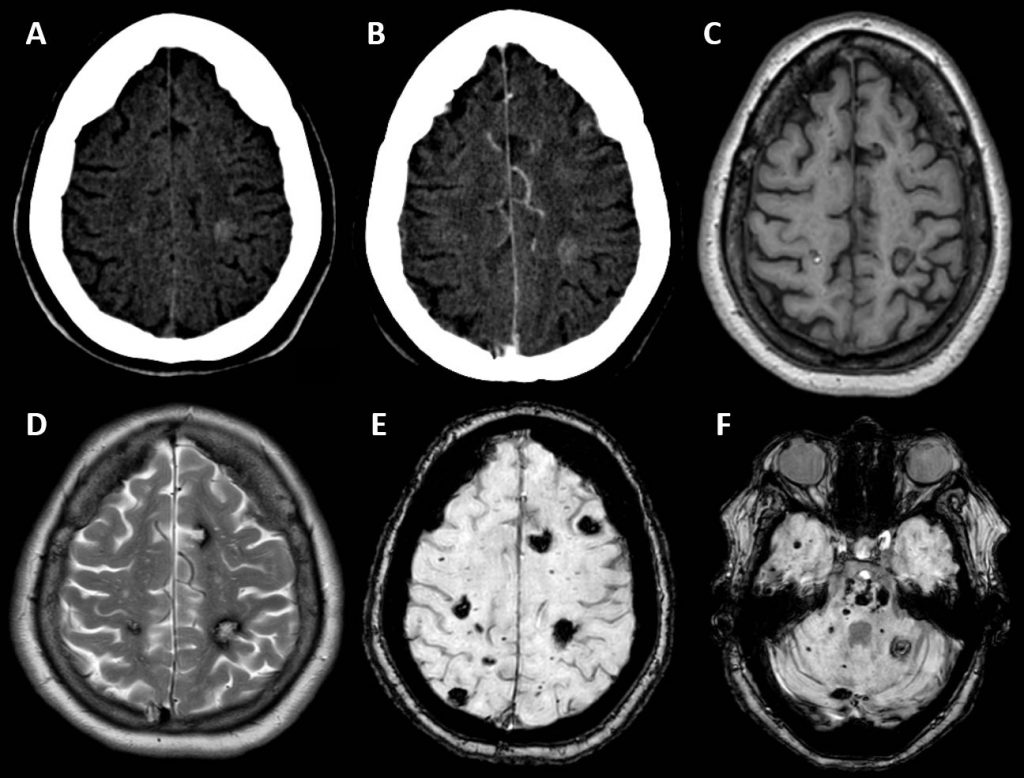

A: TC, axial: Lesión discretamente hiperdensa y mal definida en el estudio basal.

B: TC con CIV, axial: No se produce realce tras la administración de contraste.

C: T1, axial:Presencia de varias lesiones isointensas con ribete periférico hipointenso. Una de estas, en el hemisferio derecho presenta un centro hiperintenso, que le confiere aspecto de “palomita de maíz”.

D: T2, axial: Múltiples lesiones hiperintensas con ribete marcadamente hipointenso.

E, F: Susceptibilidad magnética (SWI), axial a diferentes niveles: Las lesiones se hacen más llamativas y se objetivan otras de tamaño milimétrico que no se apreciaban en las otras secuencias, de forma generalizada por todo el parénquima. Estas lesiones son marcadamente hipointensas, lo que se traduce en  restos de hemosiderina secundarios a múltiples microsangrados.